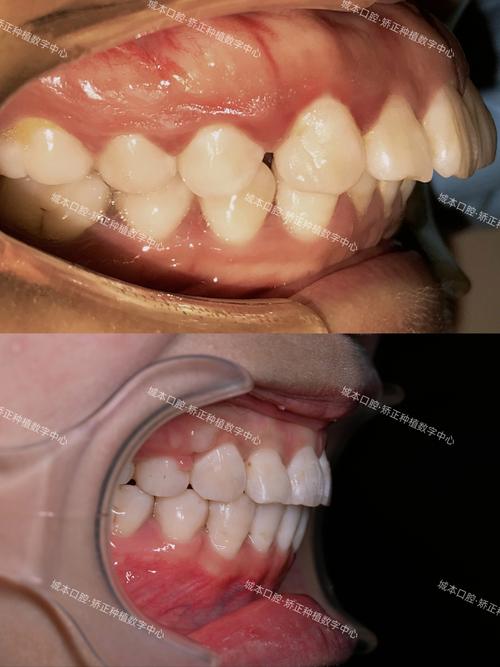

正畸尖牙牙根凸出是指在正畸治疗过程中,由于先天因素或后天干预影响,导致尖牙牙根在牙槽骨内的位置发生异常偏移,表现为牙根唇侧或腭侧超出正常解剖范围,牙槽骨壁可能变薄甚至穿孔,其成因可分为先天性与后天性两大类:

牙根凸出可能导致尖牙牙冠位置异常(如低位、扭转),影响牙列整齐度;若双侧尖牙牙根不对称凸出,可能破坏牙弓对称性,导致中线偏移、咬合紊乱。

- 视诊与触诊:观察尖牙牙龈区是否有隆起、颜色异常(发白或泛红),用手指尖按压唇侧牙槽骨,感知是否有硬性凸起;检查牙冠是否有扭转、低位,牙龈形态是否对称。